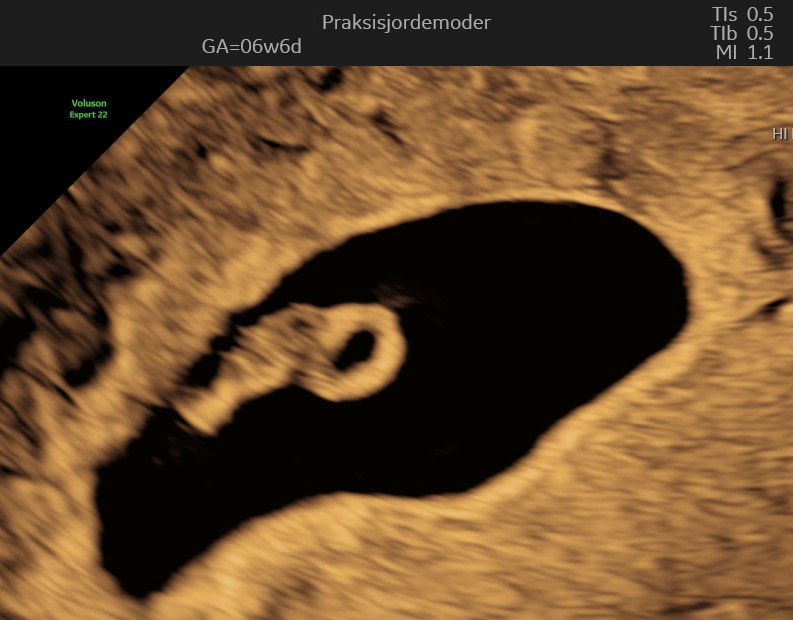

(6+0 til 6+6)

Embryoet er nu omkring 1 cm langt. Arm- og benknopper bliver tydeligere, og vigtige organer som lever og mave begynder at dannes. Navlestrengen fungerer nu og transporterer næring og affaldsstoffer mellem dig og barnet.

I uge 7 er din lille baby omkring 1,1 cm langt, omtrent på størrelse med et blåbær. Der sker mange vigtige udviklinger denne uge: